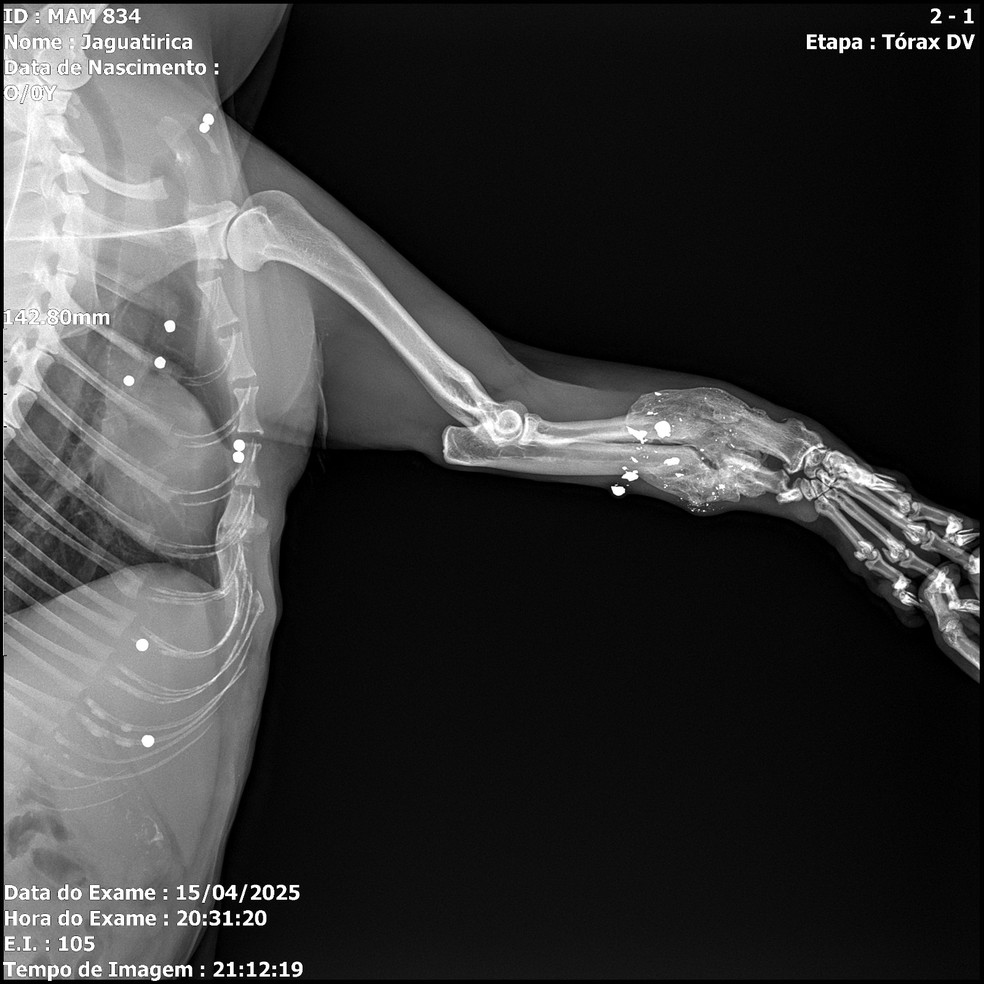

Uma jaguatirica foi resgatada no último dia 15 na região da Serra das Almas, em Trajano de Moraes, no Norte Fluminense. O animal — um macho adulto — tinha ferimentos de mais de 20 projéteis, além de fratura em na pata dianteira direita, provavelmente vítima de uma armadilha conhecida como trabuco, ocorridos dias antes do resgate, constatados por exame de raio-x. O caso foi divulgado nesta quarta-feira.

Depois de uma cirurgia em que foram retirados 23 projéteis de chumbo, um ainda está alojado perto do globo ocular: para retirá-lo, será preciso um novo procedimento cirúrgico, que depende de mais exames para apontarem a localização exata do objeto. Outras duas balas na região do tórax não serão retiradas, para não arriscar a vida do animal.

— Por que a gente sabe que foi um trabuco? Os tiros foram numa direção só. A concentração dos projéteis está na parte de barriga e do tórax — observa Paula, coordenadora de veterinária do IBW. — O animal estava magro. Para passar pela cirurgia, passou quatro dias se estabilizando, se alimentando muito bem e retiramos a maioria dos projéteis.

— Está num recinto mais contido, justamente pela pata quebrada, para se restabelecer e não gastar muita energia, porque vai passar por uma cirurgia mais crítica, que talvez seja nesta semana ainda. Depois vamos começar a ver placa e pino para colocar na pata dele — explica a veterinária.